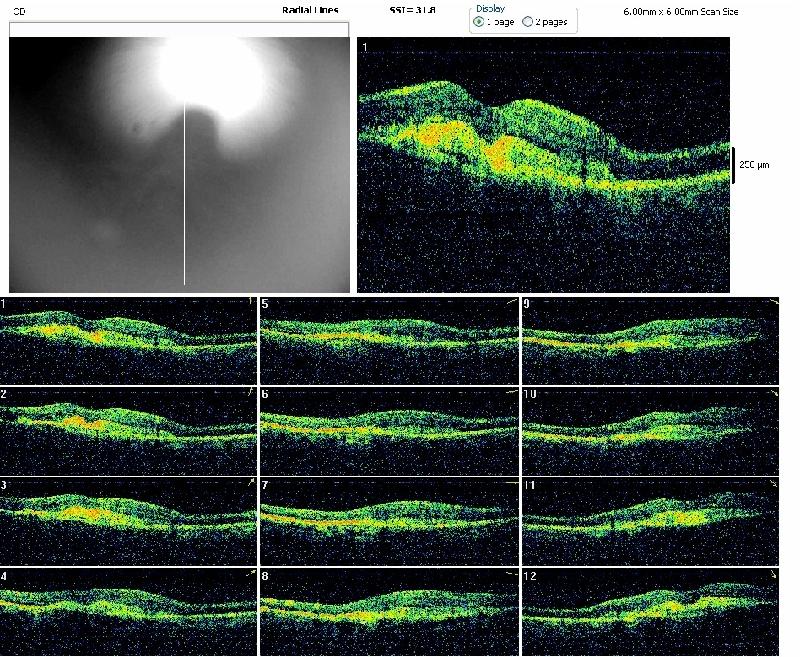

REPERTOIRES ANGIOGRAPHIES

Chaque dossier correspond à un cas dans lequel peuvent se trouver plusieurs examens à des dates différentes.

Path: /3101-20091224-01/18-08-2010/slides